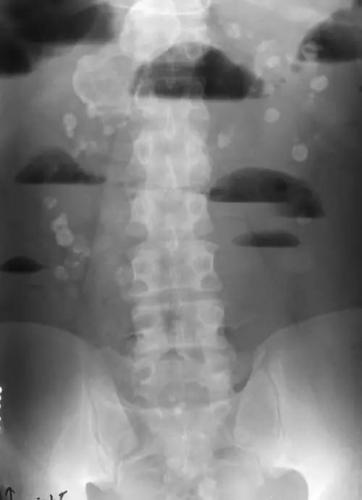

门诊dr腹部立位片提示:肠管积气,多个气液平面.

入院检查见立位腹部平片阶梯排列的气液平面.

肠梗阻为什么会出现气液平面

气液平面x线图片

气液平面